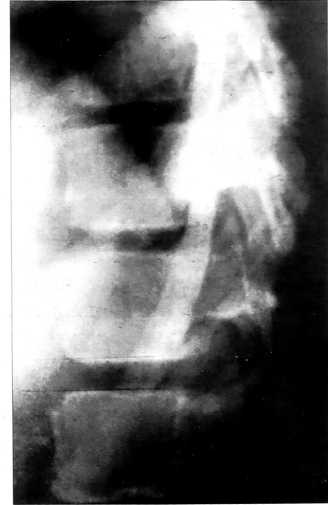

В 8-летнем возрасте больного К. беспокоило непостоянное чувство усталости в верхнепоясничном отделе позвоночника, проходившее после ночного отдыха. На произведенных спондилограммах отмечались вогнуто-выпуклые контуры замыкательных пластинок тел позвонков, утолщение контуров пластинок в дорсальных отделах, в проекции студенистого ядра межпозвонкового диска, бутылкообразная форма межпозвонковых пространств (рис. 3, а). При динамическом наблюдении отмечалось постепенное изменение характера жалоб: периодическое чувство усталости в поясничном отделе позвоночника сменилось постоянным, затем присоединился болевой синдром. Боли появлялись после длительных динамических и статических нагрузок и, как правило, проходили после ночного отдыха. На спондилограмме, выполненной в возрасте 13 лет, отмечаются типичные для остеохондропатии нарушения морфогенеза L2-L4 позвоночных сегментов в виде грыж Шморля; высота межпозвонкового промежутка L2—L3 резко снижена (рис. 3, б).

Рис. 3. Больной К. Диспластическая деформация тел позвонков. а — вогнуто-выпуклые замыкательные пластинки тел L2-L5 позвонков в 8-летнем возрасте; б — признаки остеохондропатии в сегментах L2-L4 в 13 лет.